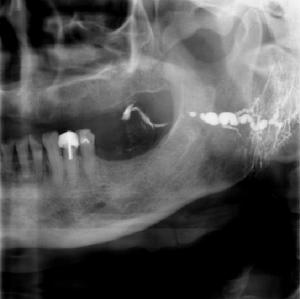

4、腮腺造影,導管是否顯示變形擴張、粗細不均及散在的小圓形“碘油池”等影像。